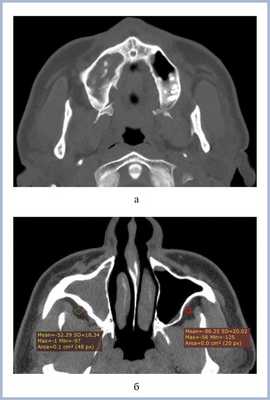

Клинический пример 1

Больной Л., 44 года, 15 лет назад терапевтическое лечение 16-го зуба с последующей перепломбировкой; 5 лет назад было осуществлено удаление 16-го зуба. В настоящее время больной обратился за помощью в ЛОР-отделение по поводу давящих болей в верхнечелюстной области справа. Больному была выполнена РКТ верхнечелюстных пазух (рис. 5, а, б), которая показала, что правая пазуха тотально заполнена мягкотканным содержимым и высокоплотным пломбировочным материалом. Отмечается утолщение костных стенок правой верхнечелюстной пазухи и прилежащей ретромаксиллярной клетчатки (–52 HU справа, –86 HU слева)

Рис. 5. Рентгеновская компьютерная томограмма верхнечелюстных пазух. Аксиальная проекция: костное окно (а), мягкотканное окно (б).

Клинический пример 2

Больная Б., 43 года, проходила исследование в отделении компьютерной томографии КОКБ по поводу объемного образования среднего уха. В качестве случайной находки выявлена правосторонняя одонтогенная киста (рис. 6, а, б; 7).

Рис. 6. Магнитно-резонансная томограмма верхнечелюстных пазух, изображения в режимах Т1 (а) и Т2 (б), аксиальная проекция.

Рис. 7. Контрольная рентгеновская компьютерная томограмма в аксиальной проекции, мягкотканный режим.